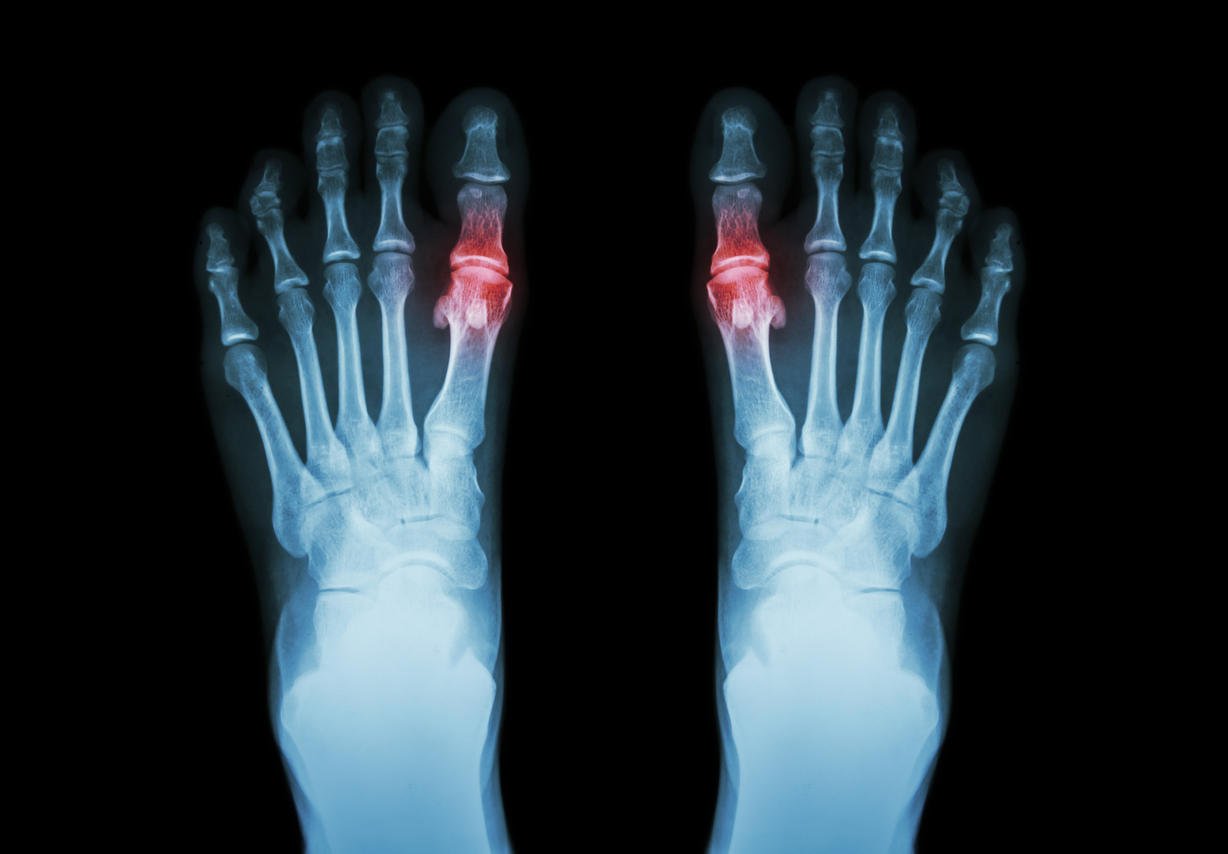

la goutte, la polyarthrite rhumatoïde (radiographie du pied et de l'arthrite au premier métatarso-phalangienne) (antécédents médicaux et scientifiques)

L'arthrose des orteils est une forme d'arthrose du pied qui touche principalement le gros orteil. Comme tous les types d'arthrose, elle est due à une usure prématurée du cartilage de l'articulation et évolue par poussées. En cas de crise de goutte, l'orteil devient très douloureux et un traitement médicamenteux doit être instauré pour soulager la douleur.

L'arthrose des orteils est provoquée par un taux élevé d'acide urique

Les purines sont des molécules présentes dans l'alimentation. On en trouve surtout dans les charcuteries, dans la viande, dans la bière et dans certains fruits de mer. Une fois dans notre corps, les purines donnent naissance à un déchet, l'acide urique. Chez les personnes qui consomment trop d'aliments riches en purines, on constate un taux élevé d'acide urique : c'est l'hyperuricémie. Au bout de plusieurs années, l'excès d'acide urique entraîne l'accumulation de petits cristaux dans les articulations, surtout au niveau des orteils. Ces cristaux sont responsables d'inflammations et de douleurs articulaires. Les douleurs ressenties pendant les crises ressemblent à celles de l'arthrose. Pour cette raison, la goutte à l'orteil est parfois appelée arthrose des orteils.